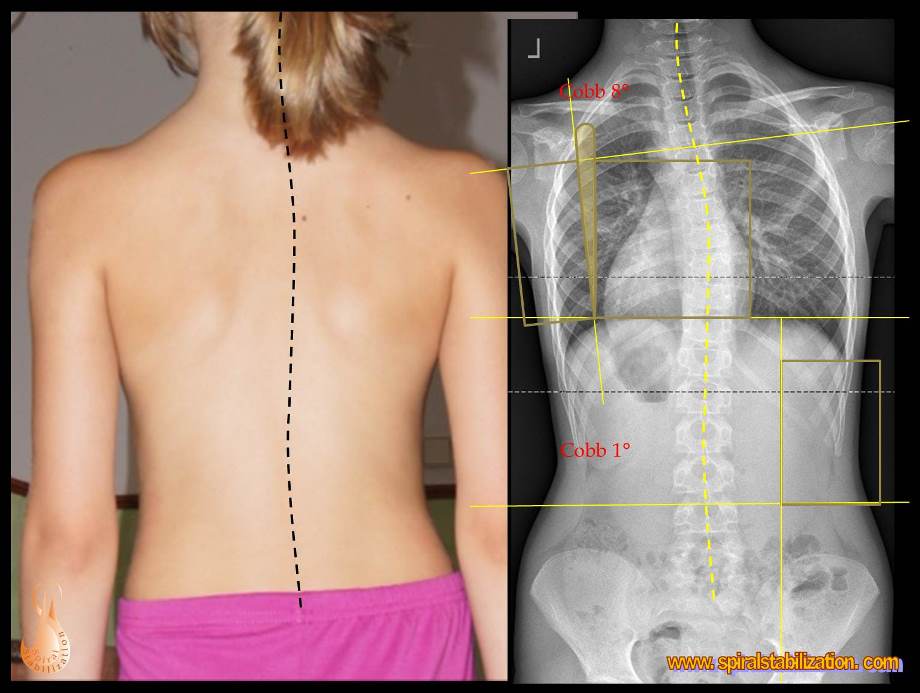

Skoliózu môžeme charakterizovať ako trojrozmernú deformitu so sklonom a posunom stavcov vo frontálnej (stranové zakrivenie), sagitálnej (zmeny fyziologickej lordózy a kyfózy) a tranzverzálnej (rotácia chrbticového stĺpca) rovine. Jednoducho povedané, je to chorobné vykrivenie chrbtice mimo jej prirodzenú krivku.

Veľkosť deformity sa hodnotí vo všetkých troch rovinách. Metódou podľa Cobba možno odčítať uhlovej zakrivenie v predozadnej projekcii (AP = Antero-posterior) a v bočnej projekcii (sagitálnej rovine). Modernými zobrazovacími metódami možno navyše v osovom reze trupu (v transversálnej rovine) odčítať rotáciu chrbtice.